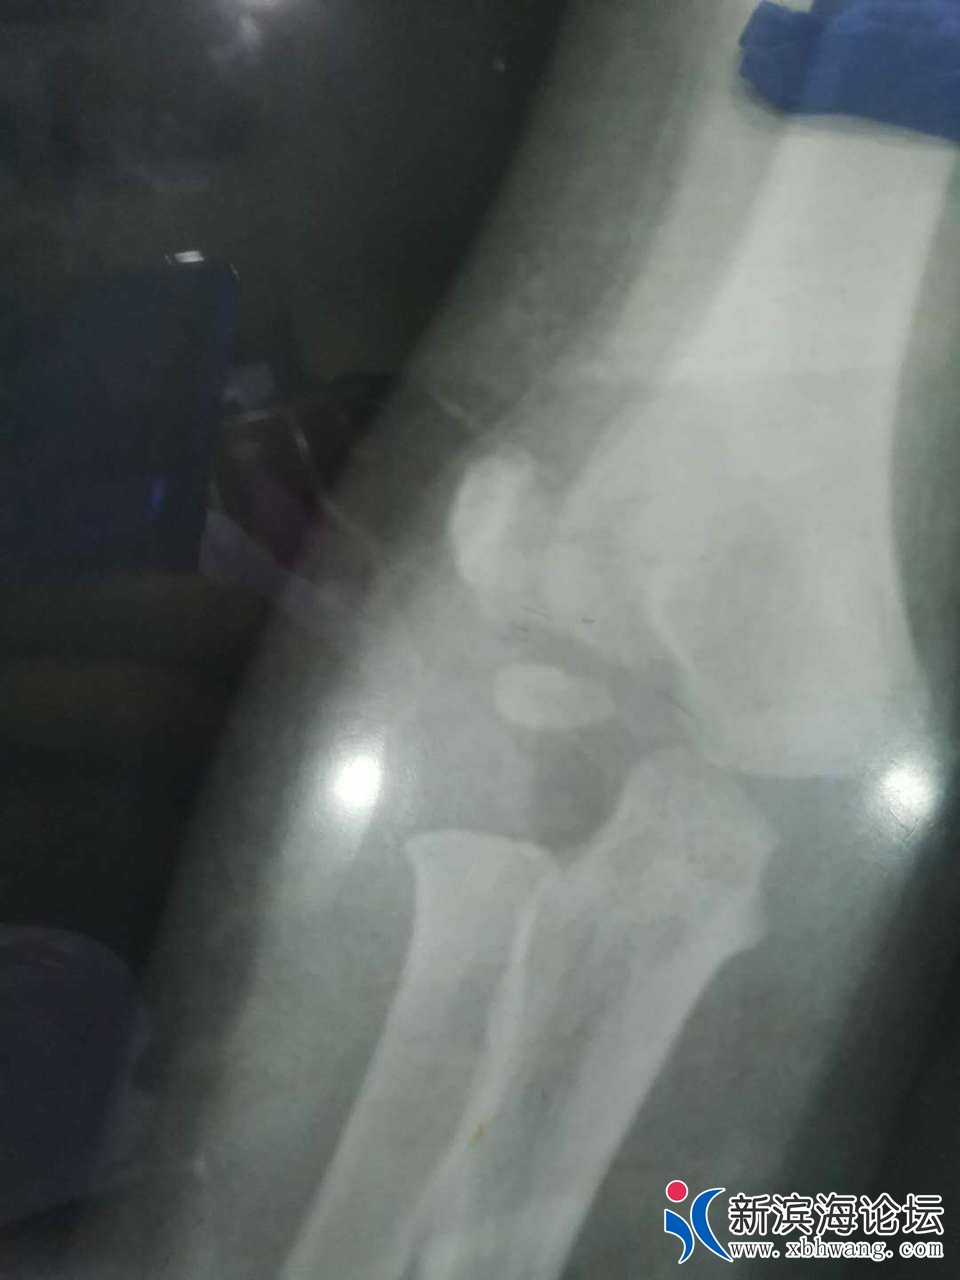

大家好 我是孩子的爸爸   3.31号晚  宝宝不小心从床上摔下来  家人比较担心  就带宝宝来到滨海第一人民医院就诊  挂完号我们等了很久才等到医生过来  简单两句话   就让我们去做血常规  再拍个片子  还嘱咐我们拍完 不用等片子出来   他可以从电脑上看  我们也不懂  就听了医生的话   等医生从电脑上看完片子  告诉我们说宝宝没有什么事  就是有点血肿  让我们回去冰敷一下就可以了  宝宝比较坚强  也没有哭  我们就相信了医生的话  带宝宝回家了  可是再到4.30号总觉得宝宝胳膊使不上力气  再次带着宝宝来到县医院复查  等来的结果却是骨折了  而且还要动手术  我们质疑了  因为3.31号晚上的片子  县医院有3个医生看过  都说没有问题   于是带着之前的片子和5月1号的片子来到其他几个医院   结果给我们的诊断都很肯定宝宝的胳膊骨折了   看过3月31号的片子  也都说  之前的片子就看的出来是骨折了  现在要动手术  而且还担心留下残疾    瞬间就感觉天塌下来了  很相信我们滨海的县级医院   结果给宝宝误诊了   现在已经一个月下来了     宝宝耽误了最佳治疗时期   滨海其他医院已经不接收这么小的宝宝 因为也错过了最佳治疗时间  我们再次来到县医院  想处理下宝宝现在的状况  可是 医院找各种理由  推脱      找到当日的值班医生  现在还不承认  说他没错  还让我们去骨科再看   真就不明白  来到医院  挂号  如果你看不了这个病  为什么让我们去做一系列的检查  还给我们诊断结果  说只是血肿  未见骨折现象     院方一味的找借口推脱  一副天不怕地不怕的样子  你们的良心不会痛吗   你们自己家里没有宝宝吗 以前总是在别人嘴里说县医院太差劲 这次,我们也算是真见到了  庸医  真的是害惨了我们一家人  特别是宝宝  他还4周岁不到  这么小  就遭这么大的罪   还有可能留下残疾的症状     真的就是黑心医院无良医生   也请有关上级领导帮忙彻查此次医疗事故  感谢不尽   下面附上宝宝两次拍的片子  前3张是3.31号晚上的   最后两张是5.1号的

你好,首先感谢你对我院工作的关心和支持,关于你反映的“县医院医生···”一事,我院高度重视,立即组织相关科室调查具体情况,患儿崔某某,男,4岁,因”意外伤"于2020年03月31日晚来我院急诊外科就诊,摄片见肱骨髁旁高密度影,考虑骨骺(小儿肘关节骨骺易与骨折混淆),初诊时不能明确,建议患儿家长三天后至我院骨科门诊复诊,患儿家长因为孩子肿痛不明显,未及时来院诊治,一个月后复查提示肱骨外科骨折,事情发生后,我院已经安排专人对接,目前正与患儿家长商讨下一步诊疗方案。最后再次感谢你对我院工作的关心和监督。